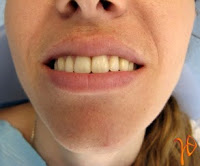

Όπως συμβαίνει στο δέρμα, υπάρχουν και στο στόμα βλάβες από ερεθισμό, οι οποίες δεν έχουν πάντοτε ανάγκη θεραπευτικής παρέμβασης (Εικόνα 1).

Εικόνα 1. α. Ερεθισμός στην υπερώα (βέλος), β. Αυτόματη επούλωση μετά από μία εβδομάδα.